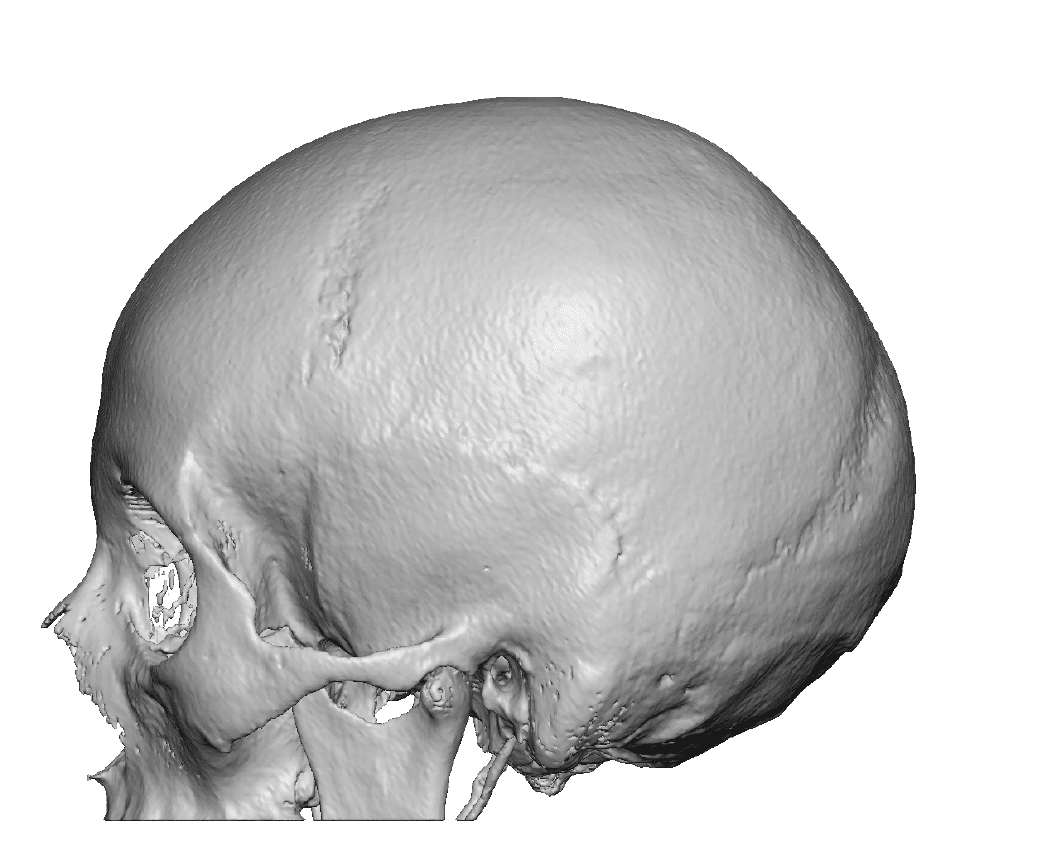

Severe narrowing skull deformity from prior sagittal craniosynostosis repair as an adult.

Complete replacement of entire skull by a custom implant with temporal fat injections.